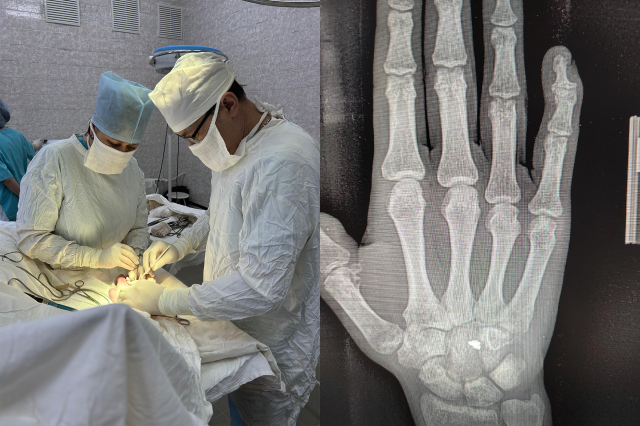

В Башкирии хирурги удалили военнослужащему осколок гранаты